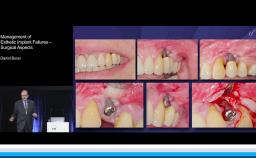

Management of Esthetic Implant Complications: Prosthetic Aspects

This lecture discusses various types of prosthesis-related implant complications that can occur in the esthetic zone. Management of esthetic implant complications are discussed via numerous case presentations. A review of the literature is presented to highlight the most common issues and causes of complications. Advice, clinical recommendations, and alternative treatment options are proposed to reduce the risk of complications in daily clinical practice.